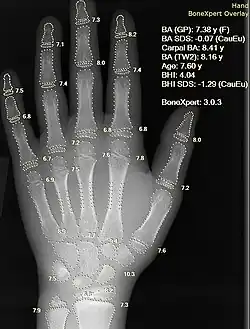

Рентгенограмма руки с автоматическим расчетом костного возраста с помощью компьютерной программы

Пионером в использовании искусственного интеллекта в здравоохранении был американский биомедицинский информатик Эдвард Х. Шортлифф. Эта область связана с использованием алгоритмов машинного обучения и искусственного интеллекта для имитации человеческого познания при анализе, интерпретации и понимании сложных медицинских данных и данных здравоохранения. В частности, ИИ — это способность компьютерных алгоритмов аппроксимировать выводы, основанные исключительно на входных данных. Программы искусственного интеллекта применяются в таких областях, как процессы диагностики, разработка протоколов лечения, разработка лекарств, персонализированная медицина, а также мониторинг и уход за пациентами. Большая часть отраслевого внимания внедрения ИИ в секторе здравоохранения сосредоточена на системах поддержки принятия клинических решений. По мере сбора большего количества данных алгоритмы машинного обучения адаптируются и обеспечивают более надежные ответы и решения. Многие компании изучают возможности использования больших данных в сфере здравоохранения. Многие компании изучают рыночные возможности в сферах «технологий оценки, хранения, управления и анализа данных», которые являются важнейшими частями отрасли здравоохранения.[18] Многие компании изучают возможности использования больших данных в сфере здравоохранения. Многие компании изучают рыночные возможности в сферах «технологий оценки, хранения, управления и анализа данных», которые являются важнейшими частями отрасли здравоохранения.[19]